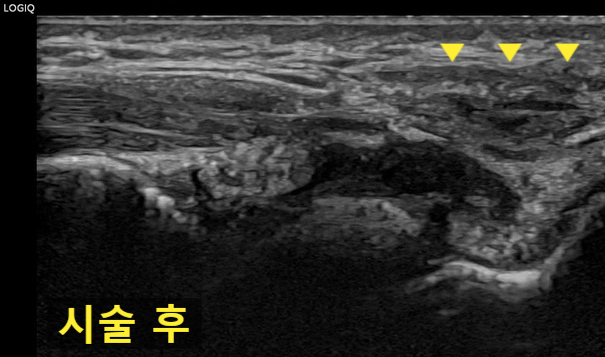

초음파 도침 시술 후 / 24년 5월 23일

2일 뒤 재확인

2일 뒤에 오셔서

다시 경혈초음파로 확인해보았습니다.

처음보다 많이 줄어들었네요.

첫날 경혈초음파와

비교해볼까요?

첫날과 비교해보면

물혹이 많이 줄어든 것이 확인됩니다.